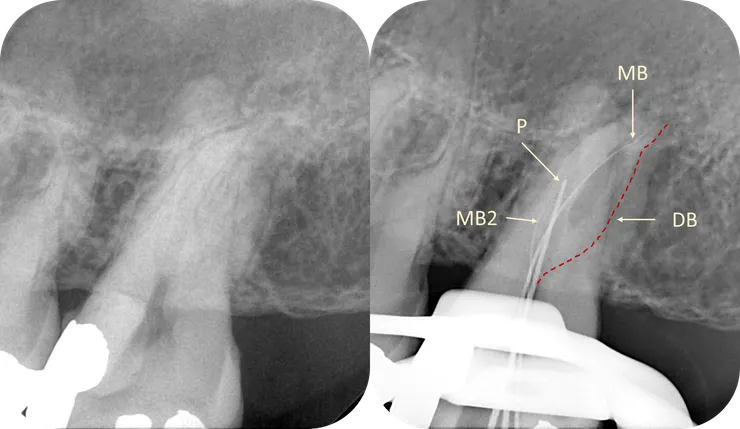

1. 從 initial PA 可以看得出來 36 & 37 的 canal 都細小鈣化到看不到。

而本篇 focus 在 37 的 ML canal.

如同開場白強調的,任何 case 在開始前,務必、千萬、一定要先看清楚 root form (橘色虛線) & canal path (紅線)!

就算 canal 鈣化到看不到,也可以依據 root form 來推測出 canal 可能的走向。

如右圖所示,從依據 root form 推測出的 canal path 看來,原本的路徑似乎偏移不大,是不是繼續往下鑽就可以了呢?

第二個 case 的起始點是這樣,前一位醫師已經找到了 P, MB 以及 MB2.

DB 則卡在半路下不去。

如圖所示,這次我們把重點擺在 DB canal.

先畫出 root form & canal path.